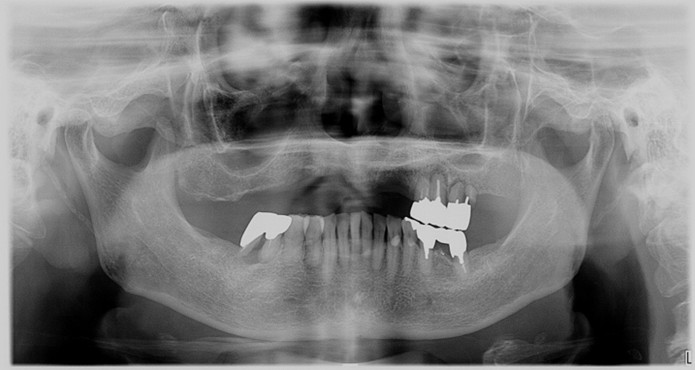

症例1

| 術前 | 術後 |

| ご来院時の主訴 | 入れ歯を入れたが落ちてくる。 インプラントの話を聞いたので入れ歯じゃなくてインプラントをしたい。 |

| 年代・性別 | 70代 女性 |

| 治療部位 | 上顎7〜7 |

| 治療費用 | 2,420,000円 |

| 手術回数 | 2回 |

| 治療期間 | 25か月 |

| 手術時間 | 90分×2回 |

| 治療回数 | 28回 |